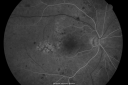

BDR and Diabetic Macular Edema with Fresh Laser Right Eye

60-year old man OD 20/60, OS 20/50 worsening vision both eyes